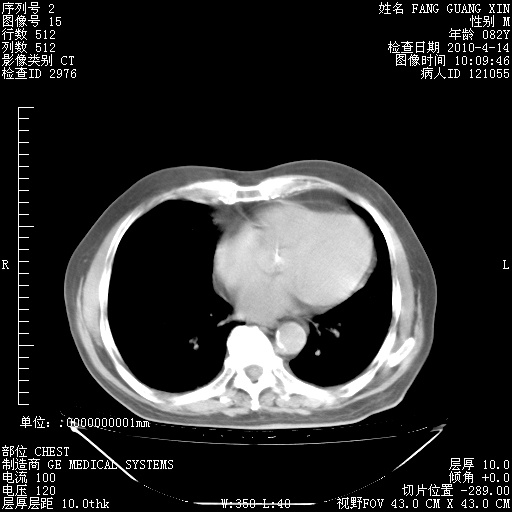

4月14日肺部CT

肺部CT平扫未见异常。

4月28日肺部CT——再次出现类似去年5月9日——透光度降低,(影像科认为)“间质性”改变。

4月28日肺部CT——再次出现类似去年5月9日——透光度降低,“间质性”改变。